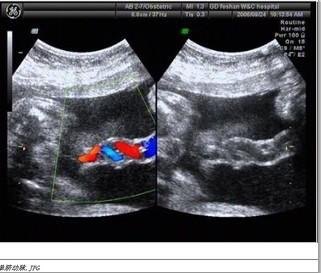

定義單臍動脈是指胎兒的臍帶血管只有一條臍動脈一條靜脈現(xiàn)象。一般情況下,胎兒的臍帶血管有2條臍動脈,1條臍靜脈。而胎兒只有1條臍動脈,1條靜脈叫做單臍動脈。 形成原因臍帶的病理性變化,其結(jié)構(gòu)變化可能是孕卵的發(fā)育缺陷。這些變化可分為以下幾種。其發(fā)生有二種學(xué)說:一種學(xué)說認為是先天性未發(fā)育,從胚胎發(fā)育開始就只有一條臍動脈;另一種學(xué)說是胚胎開始發(fā)育時存在二支臍動脈,但在以后發(fā)育過程中,一支臍動脈繼發(fā)性萎縮而消失。FOX認為這兩種可能性都存在。造成單臍動脈的原因不同,其預(yù)后也有差異。如Atshuler等報道4138例分娩中,單臍動脈19例(0.46%)。另一方面,早期胚胎伴有單臍動脈者多合并許多染色體異?;蚴褂眠^致畸藥如反應(yīng)停等,多數(shù)無心畸形常合并單臍動脈。 病理分析一條臍動脈缺如(單臍動脈)相對常見,在單胎活產(chǎn)嬰兒發(fā)生率為0.46%,多胎妊娠中為0.8%,染色體畸形的新生兒中為6.1-11.3%。13三體和18三體最常受累,而21三體和性染色體異常很少出現(xiàn)單臍動脈。在伴有單臍動脈的多數(shù)非整倍體胎兒,超聲可發(fā)現(xiàn)其他結(jié)構(gòu)異常,此時應(yīng)進行染色體核型分析。單臍動脈應(yīng)視為“高危”妊娠進行嚴密的產(chǎn)科評價和隨訪觀察,因為這些胎兒有先心病,早產(chǎn)、體重低,缺氧。腎病的危險性增加。 單臍動脈干擾了胚胎發(fā)育過程中的血液供應(yīng),可引起胎兒心血管系統(tǒng)、中樞神經(jīng)系統(tǒng)、胃腸道、骨骼系統(tǒng)、泌尿生殖系統(tǒng)和胎兒肢體的發(fā)育異常。 正常臍帶應(yīng)有兩條臍動脈,一條臍靜脈;如果只有一條臍動脈就稱為單臍動脈)。在胚胎時期,臍動脈由背主動脈發(fā)出的一對尿囊動脈演變而成。若一條臍動脈發(fā)育不良而萎縮,或在早期(3.0~4.0mm胚胎體蒂)暫時出現(xiàn)單臍動脈時期(即左、右臍動脈合并成一條血管)持續(xù)下去均可致單臍動脈 臍動脈 在哺乳動物胚胎發(fā)育過程中,從胎兒心臟發(fā)出,將胎兒體內(nèi)代謝廢物和代謝產(chǎn)生的二氧化碳運送至胎盤,轉(zhuǎn)移至母體的動脈叫臍動脈 臍靜脈 臍動脈中的血液是靜脈血,帶有胚胎的代謝廢物和二氧化碳,臍靜脈中的血液是動脈血,含有營養(yǎng)成分及氧氣。 叫臍靜脈 胎兒是通過胎盤與母體進行氣體及物質(zhì)交換,臍靜脈獲取氧氣、營養(yǎng)物質(zhì)、臍動脈排出二氧化碳及廢物。 正常的是彩色多普勒示一紅兩藍或兩紅一藍的彩色血流信號呈“麻花狀”排列。 而單臍動脈的是彩色多普勒血流顯示一紅一藍盤曲伴行分布。 正常臍帶是含兩根動脈和一根靜脈,那么切面就是品,單臍呢就是單動脈和一根靜脈,切面就是呂字 單臍動脈應(yīng)視為“高?!比焉镞M行嚴密的產(chǎn)科評價和隨訪觀察,單臍動脈是提示有問題的機率增大、而被列入高危。所以有條件的要做好胎兒排畸檢查,如二十周左右的系統(tǒng)b超,24周左右的胎兒超聲心動圖。28周后的系統(tǒng)b超,24周前的羊水穿刺查胎兒染色體。檢查都沒問題寶寶發(fā)育也很好,就跟蹤調(diào)查,注意胎動就可以了 .動態(tài)監(jiān)測胎兒生長發(fā)育情況即可,如果發(fā)育好羊水也正常,問題就不大。 應(yīng)對措施單臍動脈是沒法干預(yù)的、其產(chǎn)生的原因目前醫(yī)學(xué)上還沒有明確。算是一種自然性,偶然性質(zhì)的。 一般單臍動脈。排除胎兒系統(tǒng)b超、胎兒心臟、胎兒染色體這三個方面的問題.做好這三個檢查。 就沒什么問題的了。 單臍動脈是因為風險系數(shù)多少的問題、概率問題、才進入了b超的檢查項目。并不代表單臍動脈的寶寶就是有問題的。絕大多數(shù)出生的單臍寶寶是好的。單臍動脈胎兒的問題就是有異常的機率比雙臍的高十陪左右、如果你所有檢查都正常的。那么風險就和普通的胎兒差不多了。 如果有問題,在宮內(nèi)一般會發(fā)現(xiàn)的。寶寶檢查一切都正常,這個生下來所謂的畸形概率,和正常寶寶沒有多大區(qū)別。 單臍動脈主要就是要做好檢查、排除發(fā)育的異常、做好b超排畸。最小做兩次以上的三級篩查。分別是在20-23周之間一個、28-32周之間一個。還建議做個胎兒的心臟彩超、[胎兒超聲心動圖]目的是排除先天心臟病的可能的。在24-26周做最好。最好不要超過28周。有條件的還建議做胎兒染色體檢查。全正常就安心待產(chǎn)。